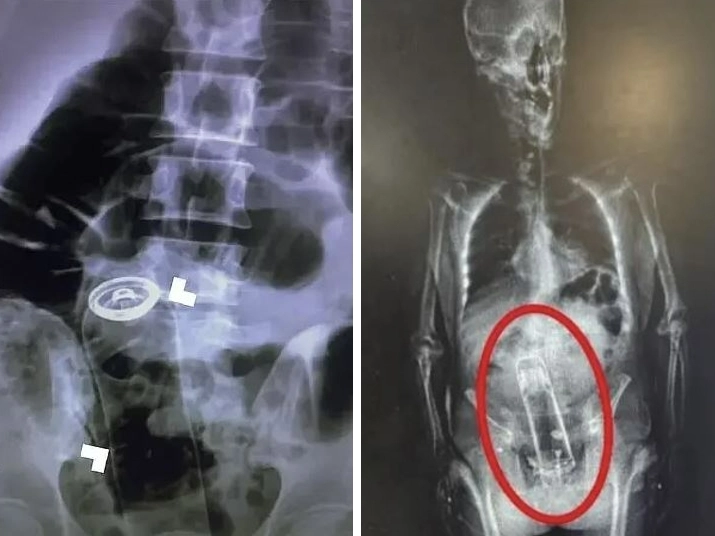

미국에서 매년 수만 명이 항문에 삽입한 이물질을 빼내지 못해 응급실을 찾는다. 데이터베이스에는 성인용품부터 야구공, 문손잡이, 보온병까지 다양한 물건이 기록돼 있다.

2023년 응급외과학술지에는 이란 남성이 항문에 삽입한 데오드란트가 소화관을 타고 올라가 응급 수술을 받은 사례가 실렸다.

지난해 미국 플로리다에서는 마약 소지 혐의로 체포된 남성의 체내에서 보온병이 발견되기도 했다.